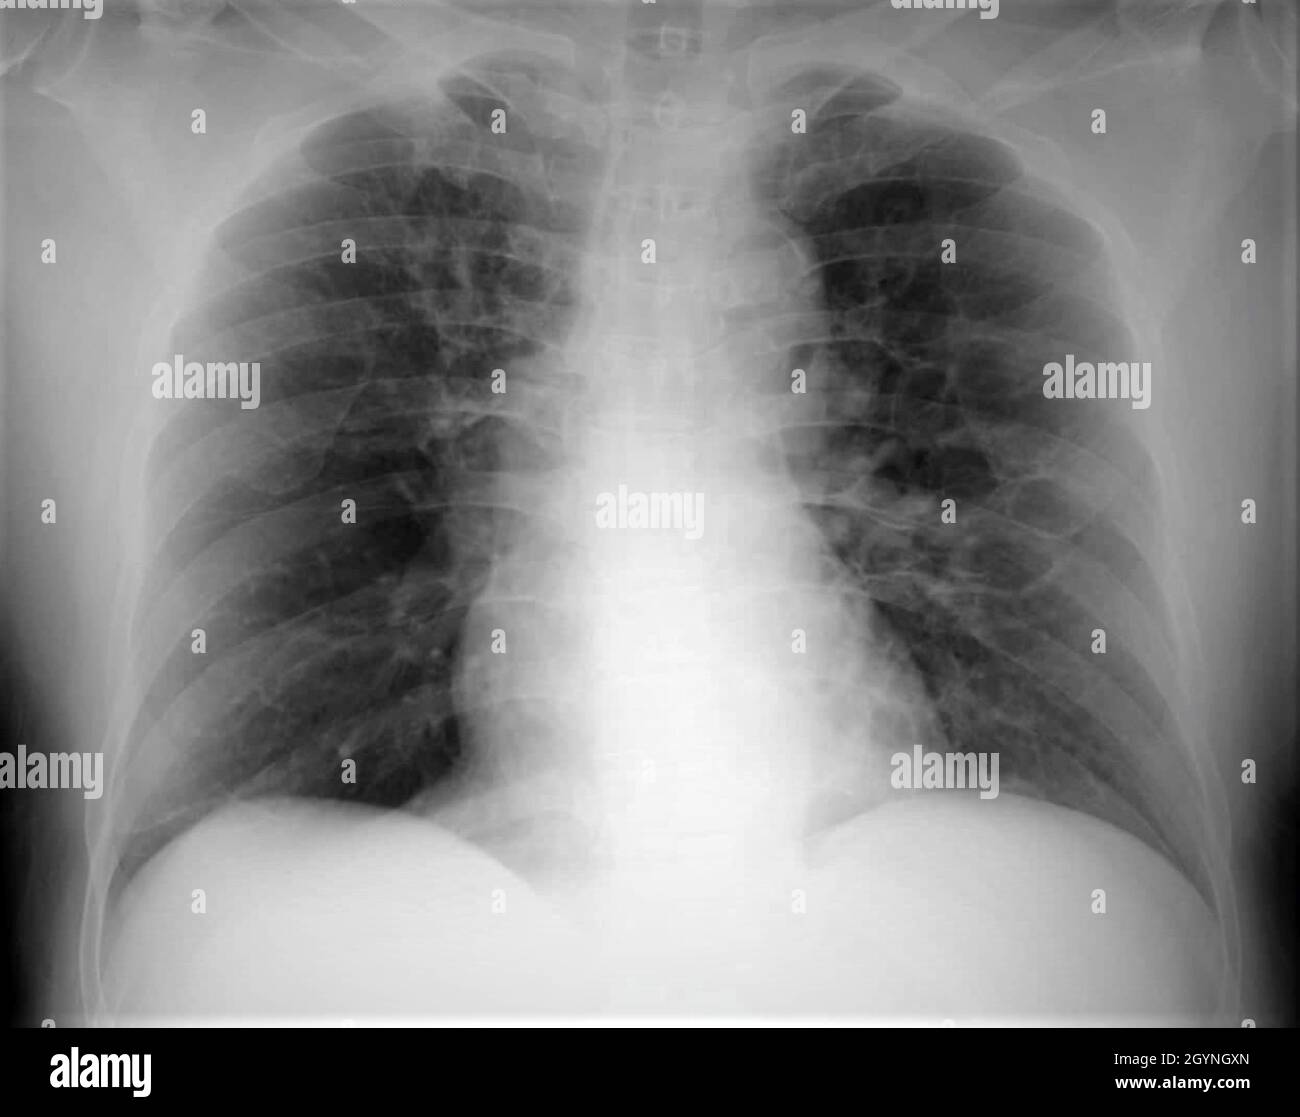

From www.alamy.com

Bronchiectasis x ray hires stock photography and images Alamy Can Bronchiectasis Be Seen On Xray In the large airways, sputum and debris can occlude the airway lumen and is manifest on ct imaging as mucous plugging. When asking a radiologist about the definition of bronchiectasis, the answer will. Chest ct scan if indicated (e.g., hemoptysis, or concern for pulmonary. Bronchiectasis and small airways disease. Bronchiectasis is dilation and destruction of larger bronchi caused by chronic. Can Bronchiectasis Be Seen On Xray.

From www.svuhradiology.ie